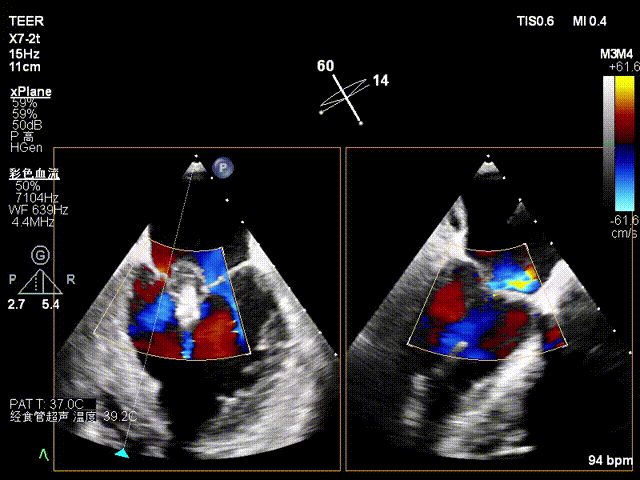

X-plane2区

X-plane2区彩色

X-plane 2区彩色